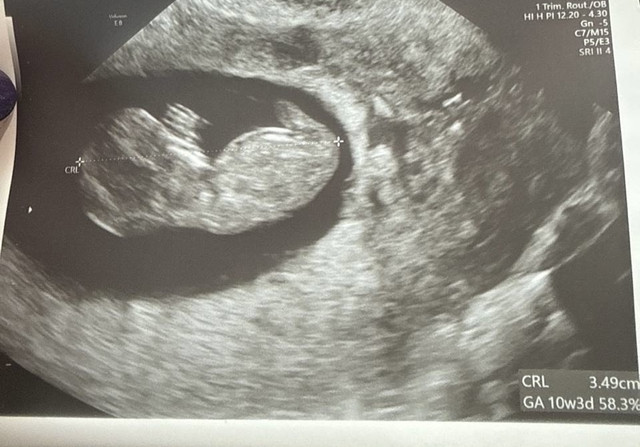

Ja po wizycie. Przenoszę tu ciążę. Wizyta trwała 50 min.

Dziecior ma 3.5 cm wychodzi 10+3.

Lekarka naprawdę mega konkretna, miła.

01.12: 10+1 - CRL 3,5 cm, FHR 175

Jestem po wizycie! Płodzik 3,36 cm, FHR 164, wielki mózg, dwie ręce, dwie nogi, RUSZAŁ SIĘ, z usg wychodzi 10+2

popłakałam się tam w ch*j ze szczęścia

Badania prenatalne 18.12 o 16:10 najpierw USG potem pobranie krwi na Pappe (tłumaczyła mi czemu cos tam dodatkowo coś tam, wszystko mi jedno)